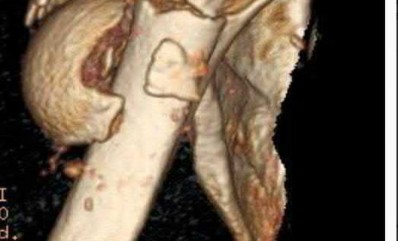

A 28-year-old male sustains a severe hyper-dorsiflexion injury to his ankle in a motor vehicle accident, resulting in a Hawkins Type III talar neck fracture. Which of the following arteries provides the predominant blood supply to the body of the talus, placing it at significant risk for avascular necrosis in this injury?

Explanation

The artery of the tarsal canal, which is a branch of the posterior tibial artery, provides the dominant blood supply to the talar body. In a Hawkins Type III fracture (talar neck fracture with subtalar and tibiotalar dislocation), the blood supply from the artery of the tarsal canal, the artery of the sinus tarsi, and capsular vessels are disrupted, leading to an avascular necrosis (AVN) rate approaching 100%.